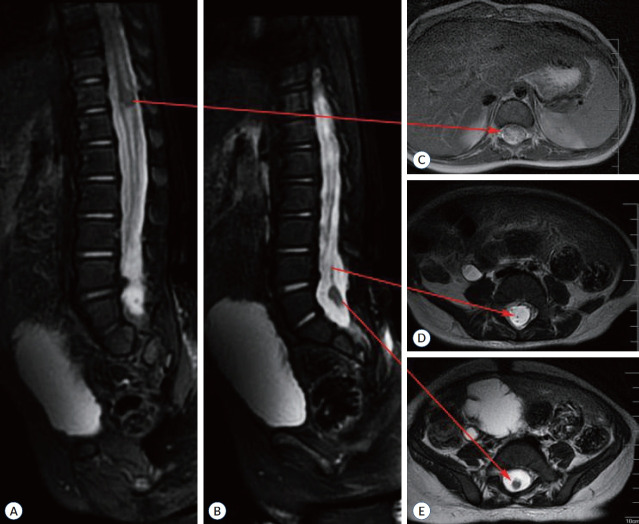

Abstract Image